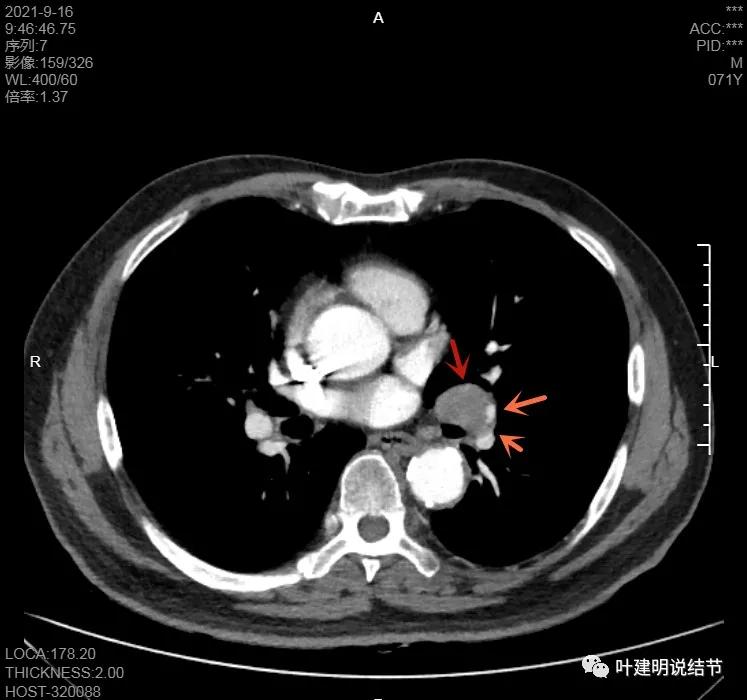

左下病灶在增强CT中强化不明显,但有肺门区肿大淋巴结,而且近3厘米大。同事叫我看片子的时候,本来只先看左下病灶处,以为是良性结节。但翻到肺门区,发现有如此大的肿大淋巴结,那这个原发灶则肯定是恶性的了!我们先来看纵隔窗的淋巴结情况:

左肺门区淋巴结肿大

肺门区淋巴结挤压附近肺血管,但似乎示见肿瘤侵犯破坏血管壁

淋巴结巨大,部分包绕肺血管,但仍未见明显侵犯血管壁

肺血管受压明显,气管内壁感觉也是光滑的

以上诸图均示肿大淋巴结挤压肺血管,但未见确切侵犯破坏,支气管内壁也感觉是光滑的,没有肿瘤突向管腔